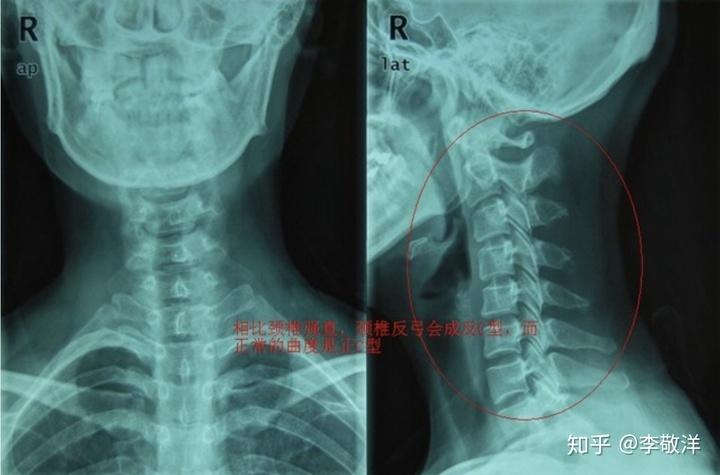

什么是颈椎反弓?